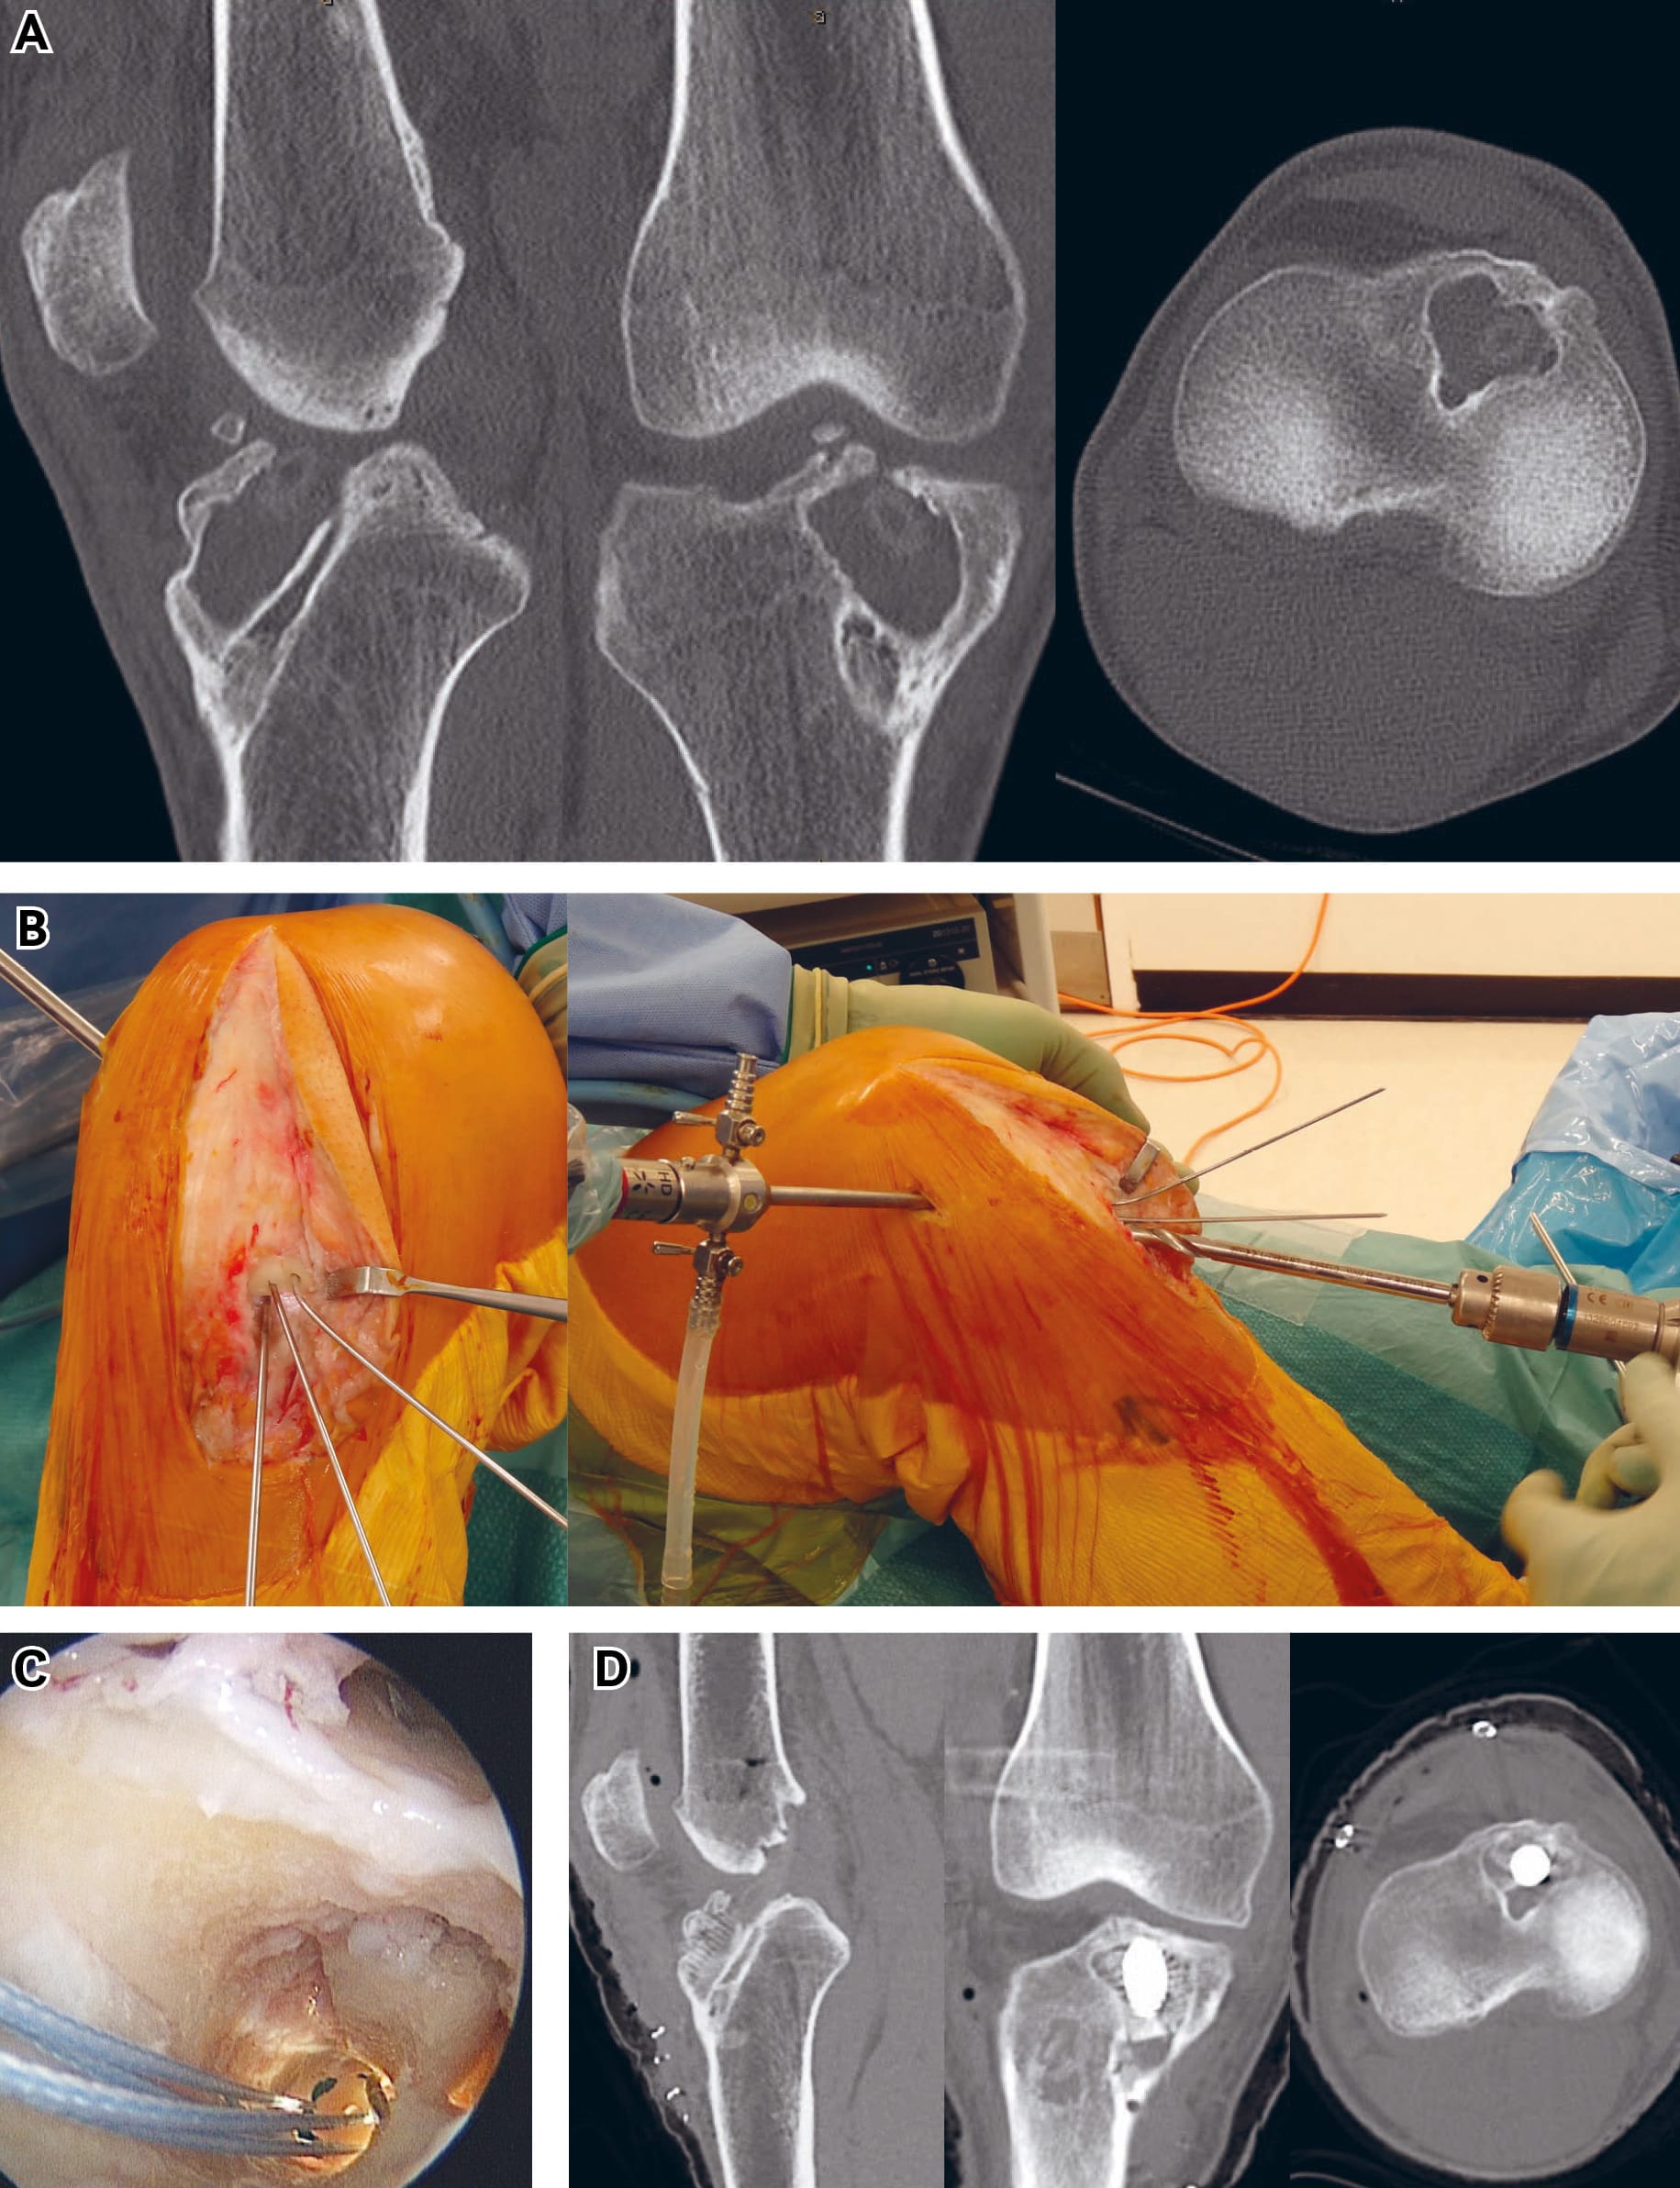

Secondly standard grafts can be used but large metal screws can be used to fill the voids in the bone. By strategic placement of such screws the graft can be pushed eccentrically to the most appropriate place within the bony tunnel.

The third option is to undertake the filling of bony defects with bone dowels, which can be harvested from the iliac crest or distal femur/proximal tibia (the former are more robust due to their cortical bone and therefore more appropriate in most cases) or, alternatively, allograft dowels may be used. A tunnel slightly undersized for the dowel is drilled to create a bleeding bone surface into which the dowel(s) are firmly impacted. Then a new tunnel can be drilled in the appropriate position for graft placement. This involves drilling through some of the newly grafted bone. The new graft will be passed and fixed within the bone-grafted tunnel with appropriate fixation. Obviously without healed bone graft the risk of instability of fixation and of the graft is greater than with a two-stage procedure. I would only undertake this situation where the patient or circumstances dictate that a two-stage procedure would be problematic. This is particularly the case with professional athletes. Really perfect surgical technique and achievement of maximal graft stability with fixation is needed. Nevertheless in this way excellent results are possible (figure 3).

Secondly, the surgeon can benefit from the ‘square peg in a round hole’ effect of rectangular bone blocks from patellar tendon or quadriceps tendon in a previously used drill hole which allows good filling of an apparently large tunnel, as pointed out by Shino et al11. Thirdly the old tunnel can be drilled eccentrically to take the centre of the new tunnel into the appropriate position. This of course enlarges the tunnel but the void created by the old tunnel can be filled with either a large graft rotated into the appropriate position, a large metal screw pushing the graft into the appropriate place which is what I usually do, or impacted bone dowels as described above.